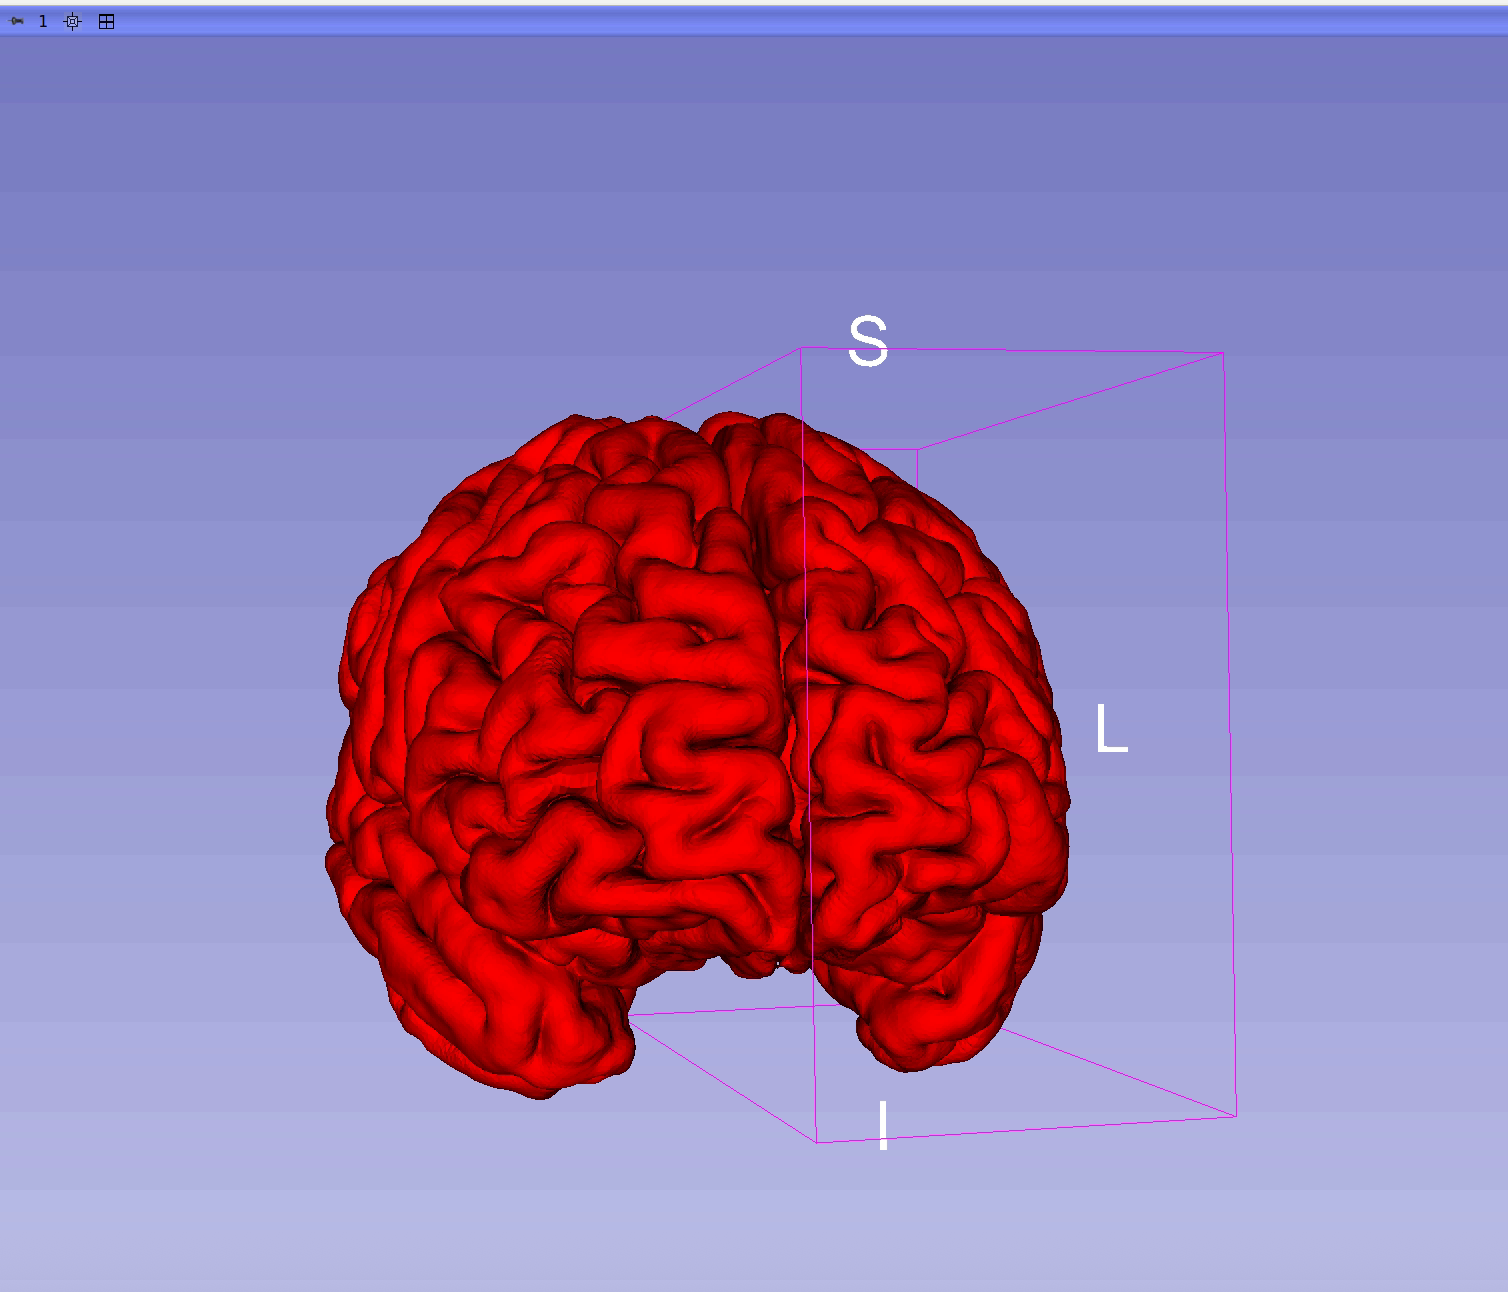

Visually validate reconstructions in 3D Slicer

Load predicted cortical surfaces into 3D Slicer and assess anatomical plausibility with expert guidance.